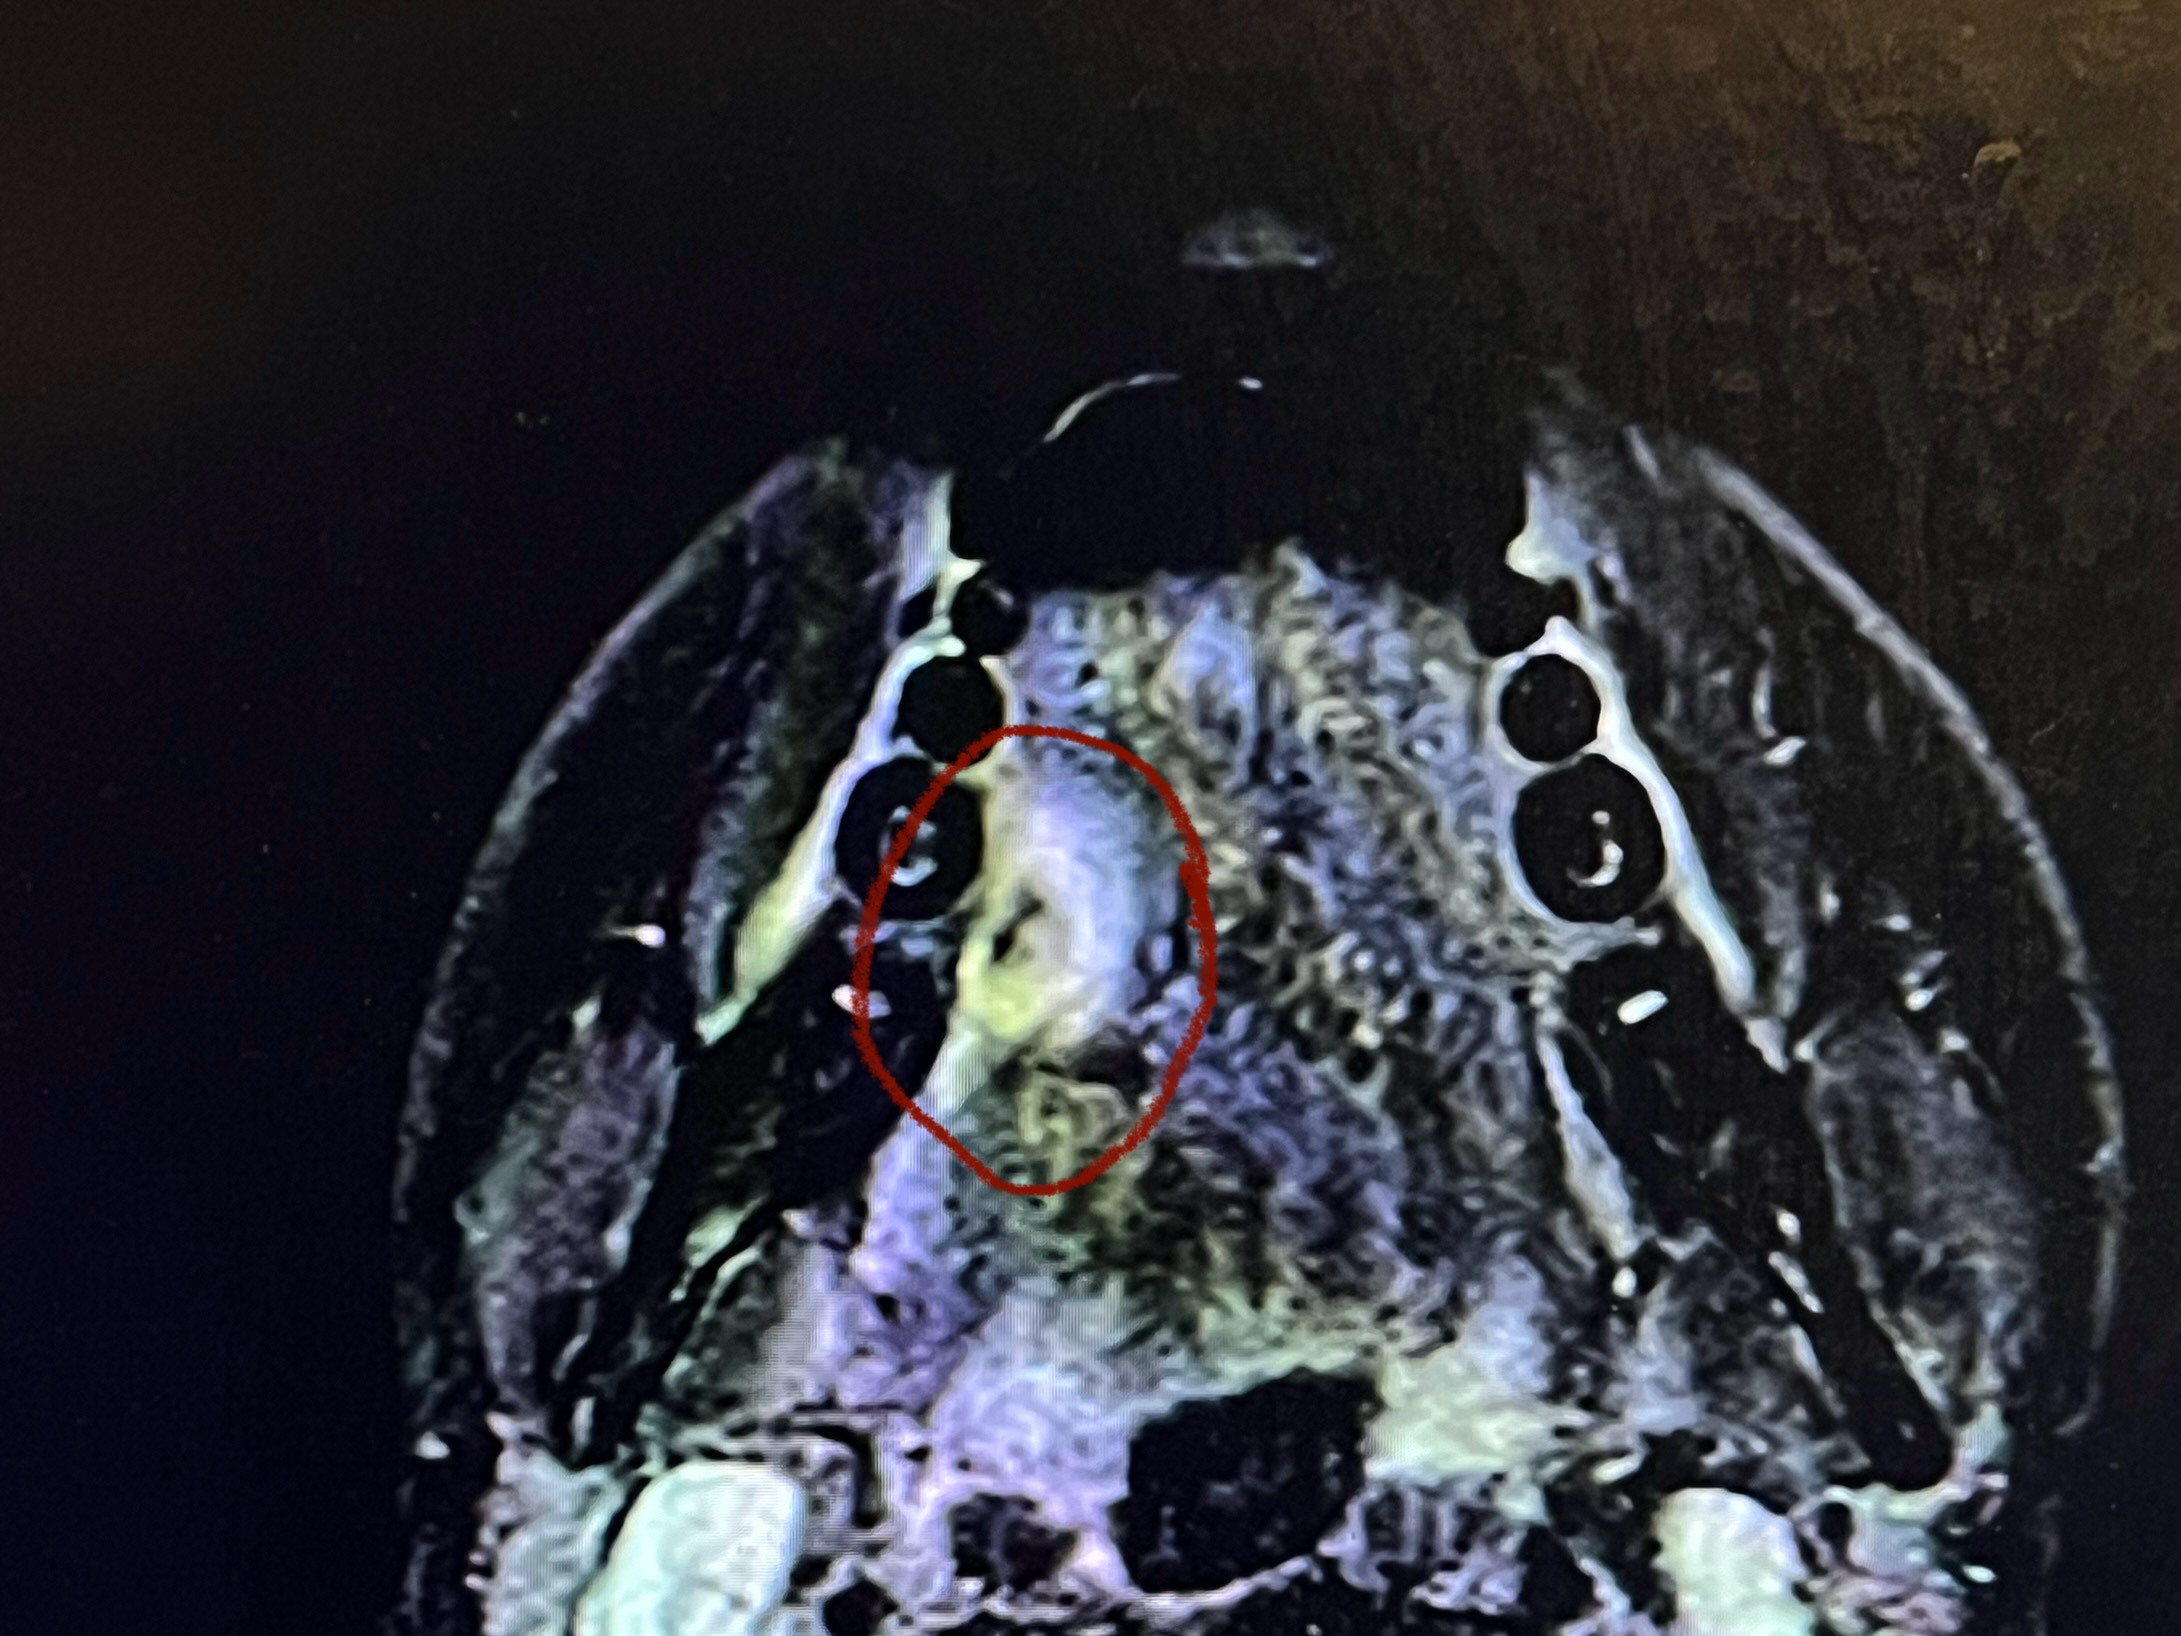

הביולוגיה של HNSCC

הבסיס הנדרש להבנת סרטן ראש-צוואר. מתחילים מהיסוד, עולה בהדרגה